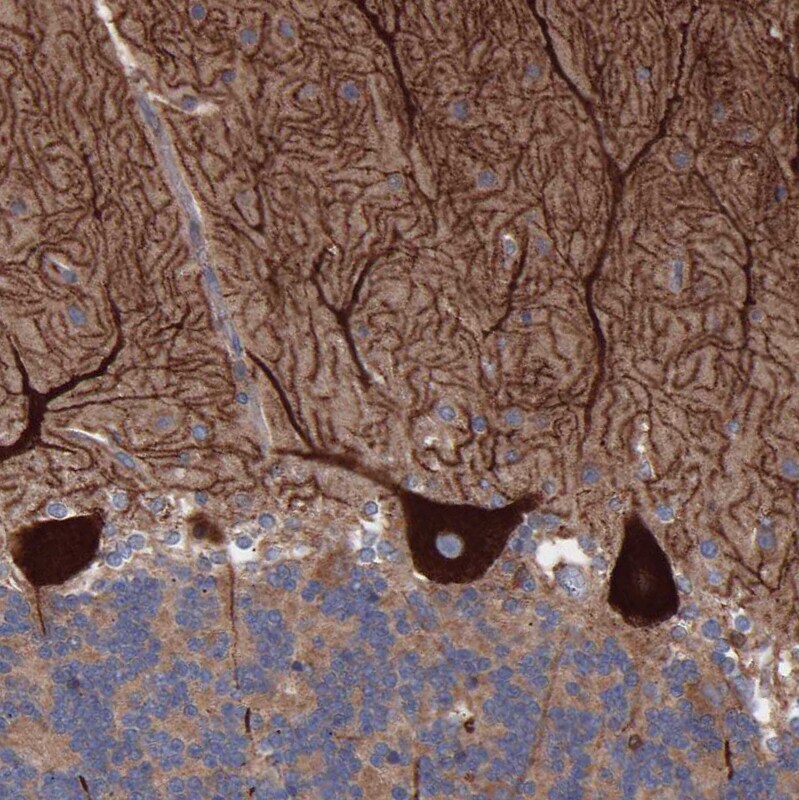

- Immunohistochemical analysis of CI091 in human cerebellum using CI091 Polyclonal Antibody (Product # PA5-53560) shows strong cytoplasmic and membranous positivity in Purkinje cells.